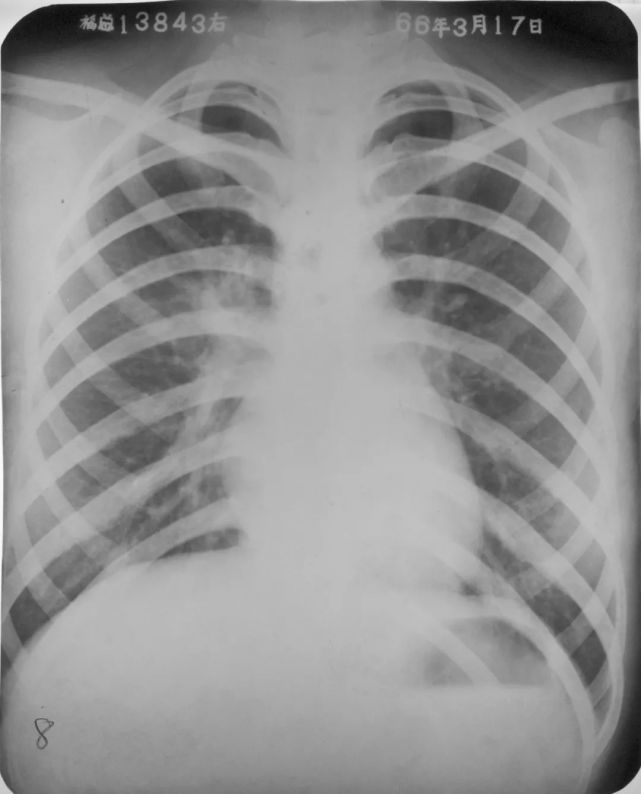

两肺支气管肺炎

图片

胸部正位片示:两肺多发不规则的小片状或斑片状边缘模糊的致密阴影,阴影密度不均,中间密度高,边缘淡,局部融合呈片状分布